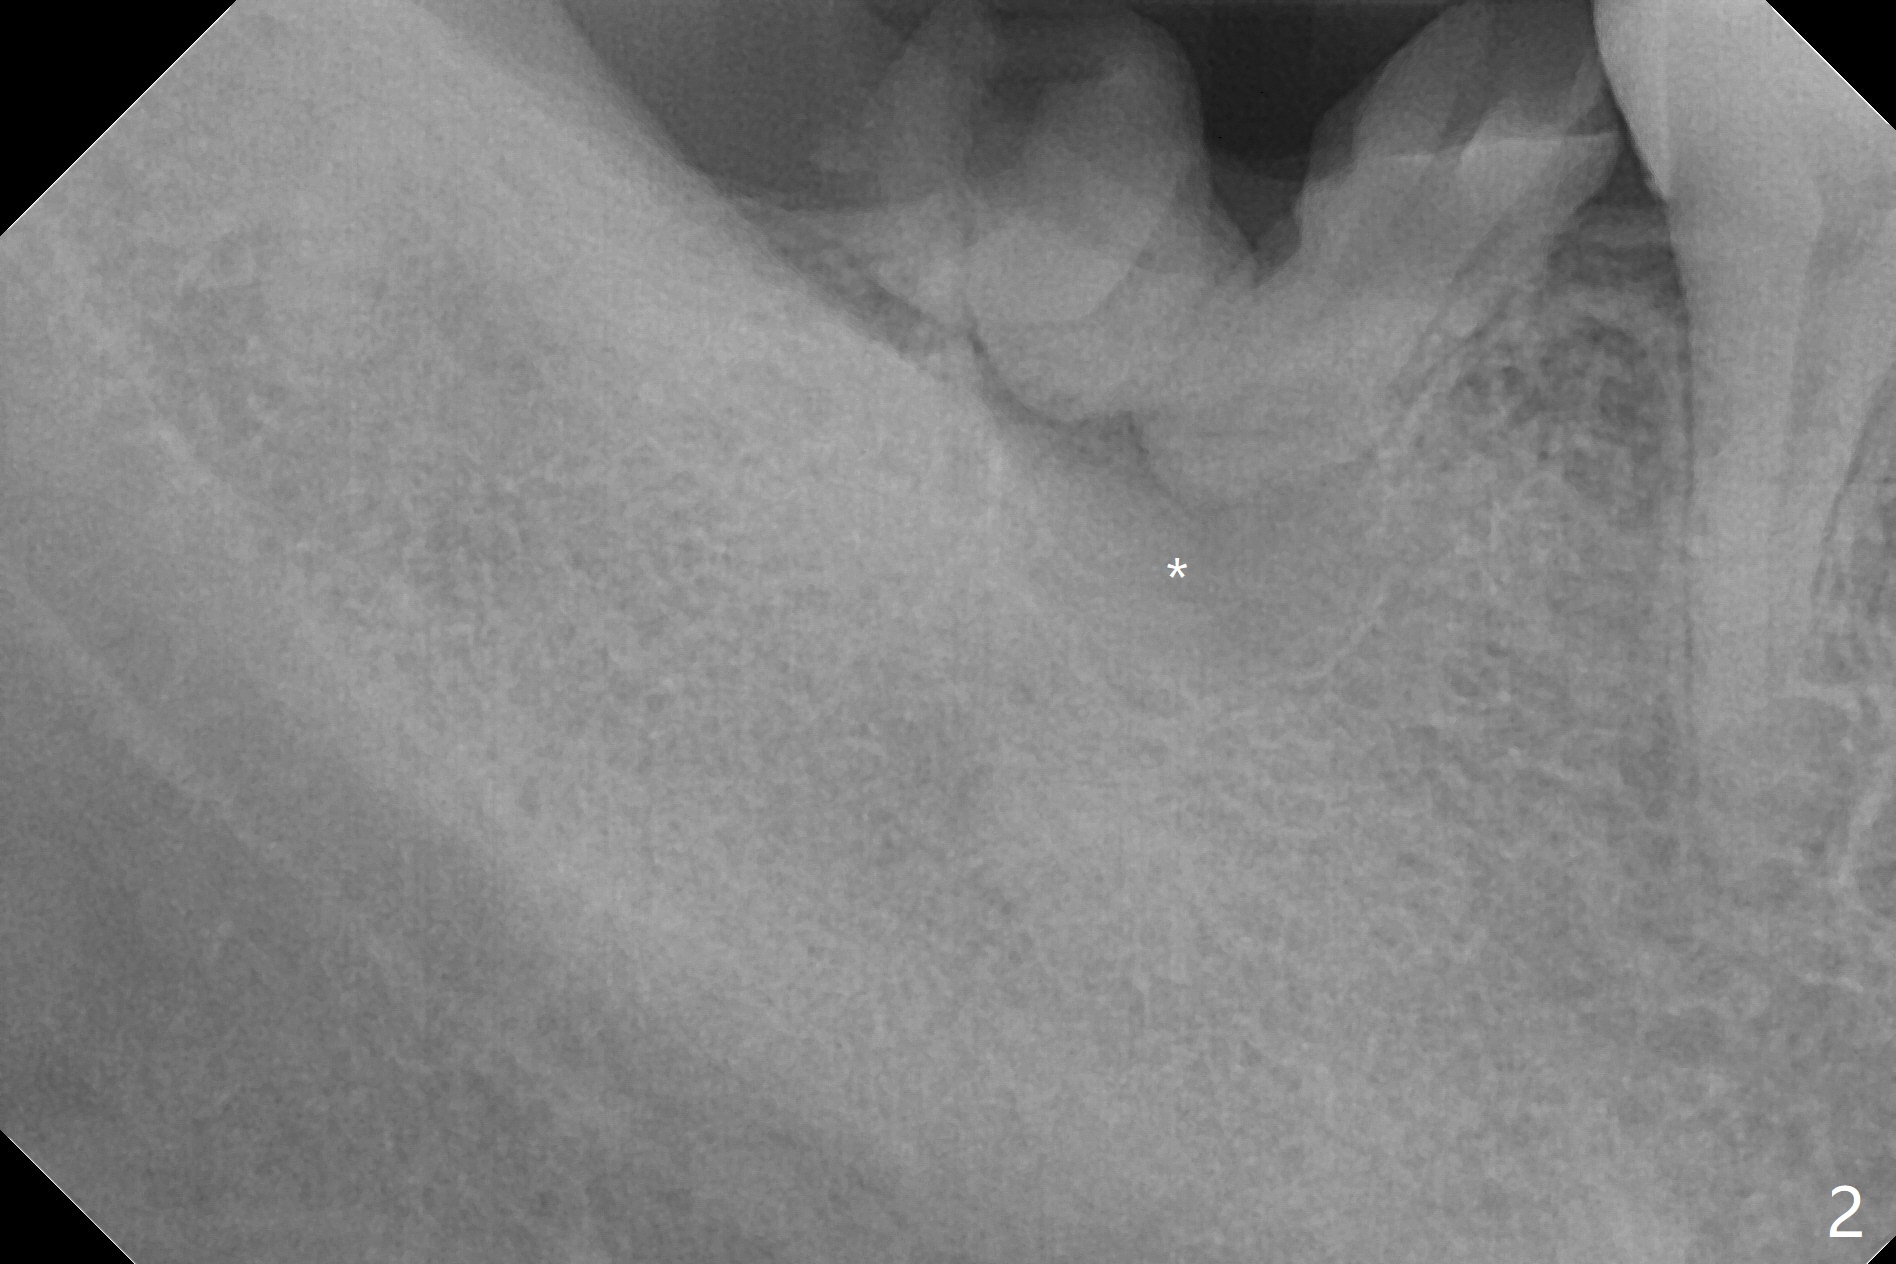

A 39-year-old man finishes orthodontic treatment without intrusion of the upper 2nd molar (Fig.1). He is reluctant for mini-implant placement for intrusion. After extraction of the tooth #31 with periapical radiolucency (Fig.2 *), a 5x11(4) mm Magicore will be placed with guide (Fig.3). Following osteointegration (Fig.4), a burn out core is going to be placed (Fig.5 brown, inside metal, outside plastic). With proper height adjustment, a provisional is fabricated around the core with acrylic (Fig.6 white). If the provisional keeps breaking down under occlusion, the case will be sent to lab for a screw retained crown with unfinished rough occlusal surface so that a thin layer restoration material able to be laid chair-side (acrylic or suction down material). Over time, the opposing tooth will be intruded (Fig.7 arrow).